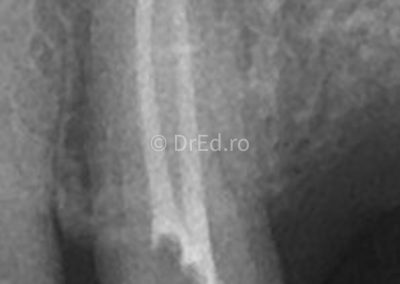

Galerie

Toate imaginile, fotografiile și radiografiile publicate pe acest site sunt protejate prin drepturi de autor și constituie proprietatea exclusivă a Dred.ro.

Aceste materiale sunt furnizate exclusiv în scop informativ și educațional și nu conțin date cu caracter personal sau informații care permit identificarea pacienților, în concordanță cu legislația privind protecția datelor cu caracter personal și GDPR.

Reproducerea, copierea, distribuirea, publicarea, transmiterea, modificarea sau orice altă utilizare, integrală ori parțială, a acestor materiale, în orice formă și prin orice mijloace, fără consimțământul prealabil scris al titularului drepturilor, este strict interzisă și poate atrage răspunderea civilă și/sau penală, în condițiile legii aplicabile privind drepturile de autor și protecția proprietății intelectuale.